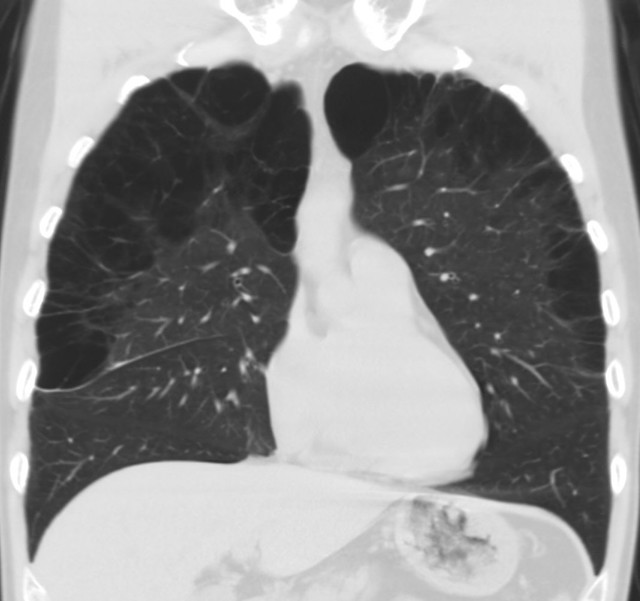

From rebelem.com

Baby Lungs REBEL EM Emergency Medicine Blog What Causes Hole In Baby Lung A pneumothorax can be caused by a blunt or penetrating chest injury, certain medical procedures, or damage from underlying lung. This causes air to leak. This causes air to leak into the space between the lung and. A pneumothorax occurs when some of the tiny air sacs (alveoli) in a baby's lung become overinflated and burst. A pneumothorax occurs when. What Causes Hole In Baby Lung.